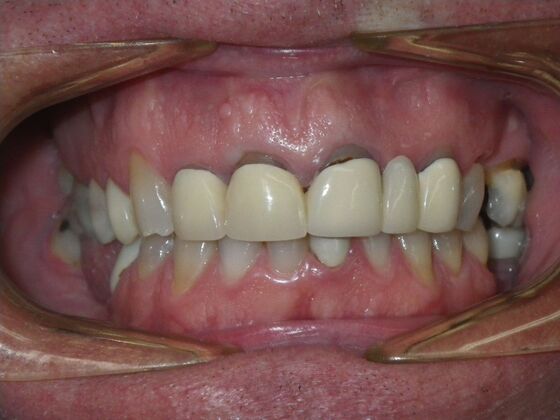

Cosmetic Changes with Veneers and Crown and Bridge: Case 5

Patient wanted to see about getting his upper front crowns replaced. He has had them for 35 plus years. Also concerns about his gums receding and the metal margins of crowns showing. Also talked with him about the need for crown lengthening which would have helped decrease the gummy smile; however, he chose not to do this. I thought just replacing the existing crowns to the existing gingival margins would be a great help. So the existing porcelain/metal crowns were removed and new all ceramic single unit crowns placed from upper right cuspid,lateral incisor and right central incisor. Then a 3-unit all ceramic bridge was placed from upper left central incisor to upper left cuspid. This patient and most of all his wife were very pleased with the end result.